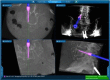

Background: Technological advances, including navigation, have been made to improve safety and accuracy of pedicle screw fixation. We evaluated the accuracy of the virtual screw placement (Stealth projection) compared to actual screw placement (intra-operative O-Arm) and examined for differences based on the distance from the reference frame.

Methods: A retrospective evaluation of prospectively collected data was conducted from January 2013 to September 2013. We evaluated thoracic and lumbosacral pedicle screws placed using intraoperative O-arm and Stealth navigation by obtaining virtual screw projections and intraoperative O-arm images after screw placement. The screw trajectory angle to the midsagittal line and superior endplate was compared in the axial and sagittal views, respectively. Percent error and paired t-test statistics were then performed.

Results: Thirty-one patients with 240 pedicle screws were analyzed. The mean angular difference between the virtual and actual image in all screws was 2.17° ± 2.20° on axial images and 2.16° ± 2.24° on sagittal images. There was excellent agreement between actual and virtual pedicle screw trajectories in the axial and sagittal plane with ICC = 0.99 (95%CI: 0.992-0.995) (p<0.001) and ICC= 0.81 (95%CI: 0.759-0.855) (p<0.001) respectively. When comparing thoracic and lumbar screws, there was a significant difference in the sagittal angulation between the two distributions. No statistical differences were found distance from the reference frame.

Conclusion: The virtual projection view is clinically accurate compared to the actual placement on intra-operative CT in both the axial and sagittal views. There is slight imprecision (~2°) in the axial and sagittal planes and a minor difference in the sagittal thoracic and lumbar angulation, although these did not affect clinical outcomes. In general, we find that pedicle screw placement using intraoperative cone beam CT and navigation to be accurate and reliable, and as such have made it a routine part of our spine practice. This study was approved by the University of Minnesota IRB (#1303E30544).